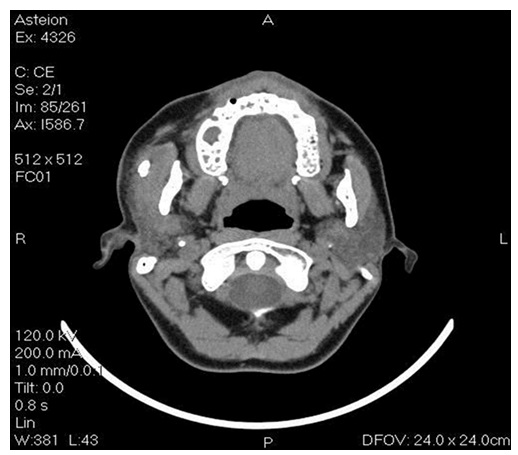

Computed tomography (CT) showed the presence of a spherical radiopaque image suggested a possible sialolith with diameter of approximately 12 mm, located superficially at the right parotid gland (Figure 2). During the initial evaluation, it was not observed the presence of this lesion in her panoramic radiograph.

Magnetic resonance (MR) imaging is the method of choice for patients with palpable masses and a strong suspicion that the lesion is neoplastic 8, however the CT is the method of optimal in patients suspicious for inflammatory disease (abscess, calculi, major salivary duct dilatation, and acute inflammation) or in patients with contraindication for MR imaging. For CT imaging both pre- and post-contrast studies must be performed in order to detect calcifications (pre-contrast) and enhancement pattern (post-contrast). In our report, the panoramic radiograph did not show any changes which may have confused other colleagues, so we requested a more accurate imaging study to facilitate the diagnosis and treatment planning. CT have information on the exact localization and extent of the lesion, addresses neighboring structures, so, after seeing that the lesion was not close to important structures (facial nerve) and its location was superficial to the parotid gland, sialolith exeresis was held. The facial nerve cannot usually be visualized by imaging, however a virtual line drawn from the lateral border of the posterior belly of the digastric muscle and the retromandibular vein to the lateral edge of the mandible can be used as an anatomical landmark 8.